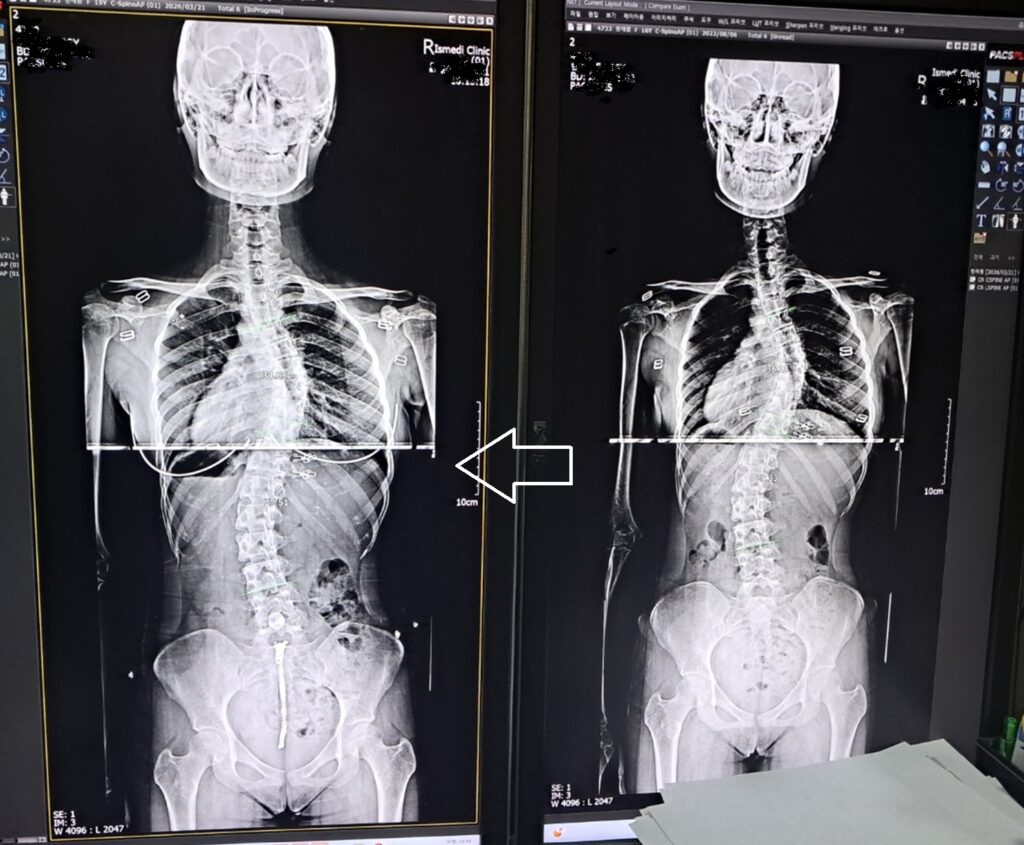

분당 허리 통증 척추측만 상담 사례

각도 36.13 -> 34.63